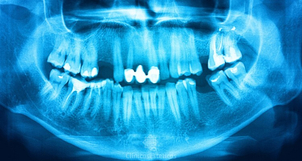

Durante la primera consulta el odontólogo realizará una completa revisión para determinar cómo es la salud bucal del paciente. Así mismo, el odontólogo realizará una completa evaluación de la dentadura del paciente, tomando en algunos casos, radiografías de la o las piezas dentales dañadas para determinar qué tipo de tratamiento es los más convenientes según sea cada caso. Si el paciente tiene alguna infección o caries, lo más probable es que se necesiten tratamientos de endodoncia antes de proceder con la reconstrucción.